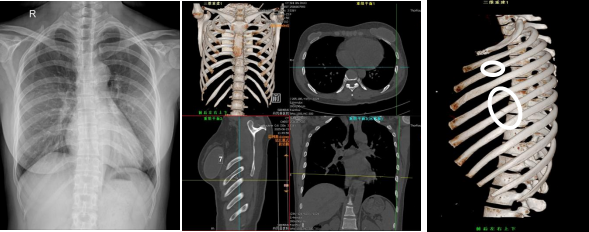

外伤后胸痛病人,胸片检查无异常,CT骨三维重建可见左侧第3、5、6、7肋骨折

大部分典型的肋骨骨折可通过多层螺旋CT薄层扫描及三维重建轻松诊断,而有些骨折,只是出现骨小梁的断裂或者骨皮质的轻度折曲,但是骨折处并无明显错位,即使是薄层CT也常常很难发现,易致漏诊、误诊。但是随着患者呼吸、转身等肢体移动,可使骨折发生错位,从而显示骨折线;或者骨折线短期一直没有发现,但过一段时间,局部血肿、炎症的吸收后,断端可见骨痂生长,表示此处曾有骨折。在胸部外伤中,首次CT三维成像和3周后三维CT复查结合分析,能更加准确显示骨折的真实情况,这在工伤鉴定或司法鉴定实践中具有重要意义。